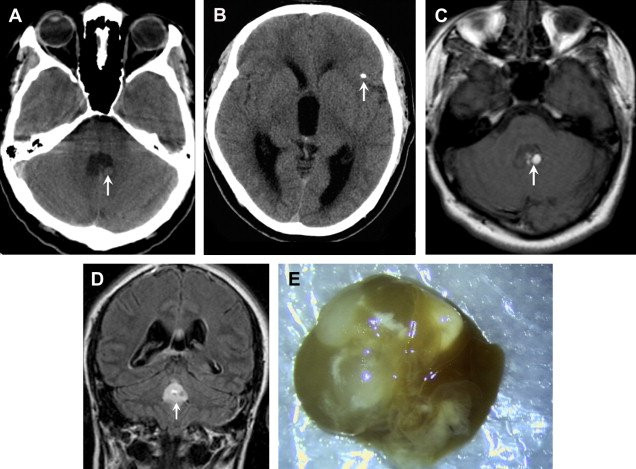

Biểu hiện của nhiễm nang sán rất phong phú, tùy thuộc vào vị trí mà các nang sán cư ngụ. Ấu trùng sán có thể đi bất kỳ cơ quan nào trong cơ thể nhưng thường tập trung nhiều ở cơ, mắt và đặc biệt là não.

Biểu hiện của sán lợn trong não dễ khiến người bệnh nhầm lẫn với một số bệnh thần kinh khác. Bởi người bệnh thường có đau nhức đầu, chóng mặt, buồn nôn, mất ngủ, trí nhớ giảm sút, bại chân tay, rối loạn cảm giác, liệt, tăng áp lực nội sọ... Vì thế, nhiều bệnh nhân có ấu trùng sán lợn trong não đến viện sau cả quá trình dài vài năm đi khám ở nhiều nơi mà không phát hiện ra bệnh.

Do ăn tiết canh, sán cư trú trong mắt người bệnh.

Do ăn tiết canh, sán cư trú trong mắt người bệnh